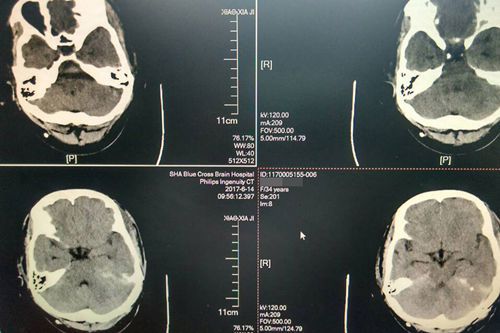

術(shù)后:CT顯示腫瘤切除,小腦幕緣、右側(cè)腦室滲出已吸收